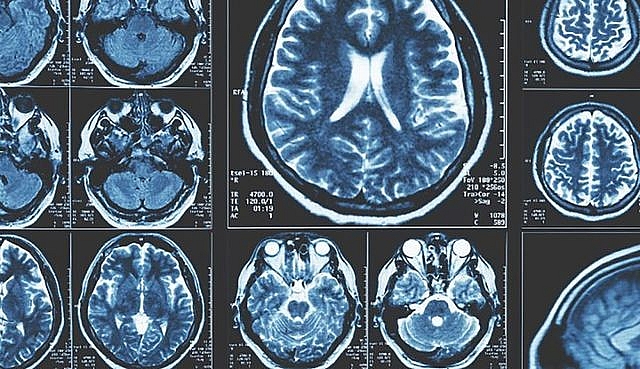

| Các nhà khoa học đang tìm cách phát hiện sớm các triệu chứng liên quan đến bệnh Parkinson. (Nguồn: Science Alert) |